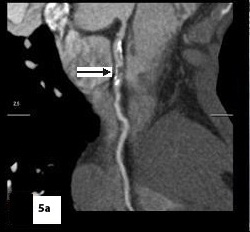

Five patients (12.5 %) had normal angiograms [Table/Fig-2,2b,3,3b], six (15%) had non-significant disease [Table/Fig-4,4b,5a,5b] and 29 patients (72.5%, 26 male & 3 female) had significant disease [Table/Fig-6a,6b],[7a,7band8] on CT coronary angiography, which was also proved on invasive angiography [Table/Fig-9]. The incidence of significant coronary detected was highest in age group of 41-60 years [Table/Fig-10].

Curved reformatted image with mixed palque

Catheter angiography image showing focal non-significant stenosis in RCA